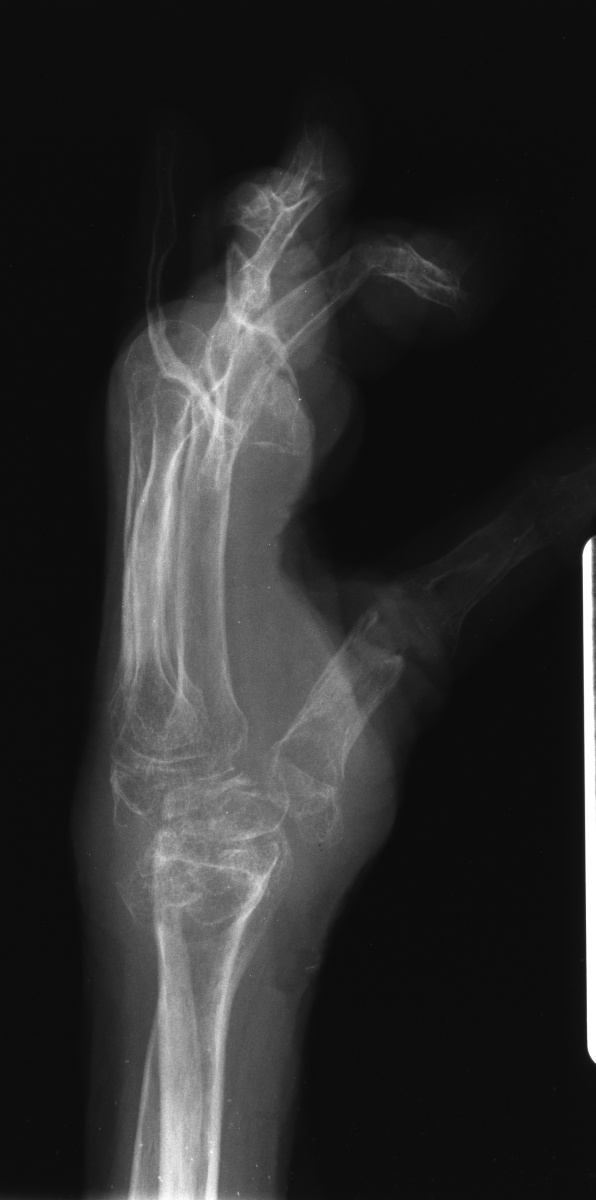

This woman has undergone multiple rheumatoid procedures elsewhere. On the right, these included right wrist fusion and MCP silicone arthroplasties. On the left, silicone arthroplaties of the thumb MCP, index and middle PIP joints and arthrodesis of the thumb IP, ring and small PIP koints. She wanted improvement of her left hand function, which was hindered by wrist pain and flail fingers.

Her left index and middle fingers are grossly unstable.

Xrays show radiocarpal collapse, proximal migration of the proximal phalanges, flail PIP joints and loss of the proximal half of the dorsal cortex of the proximal phalanges.